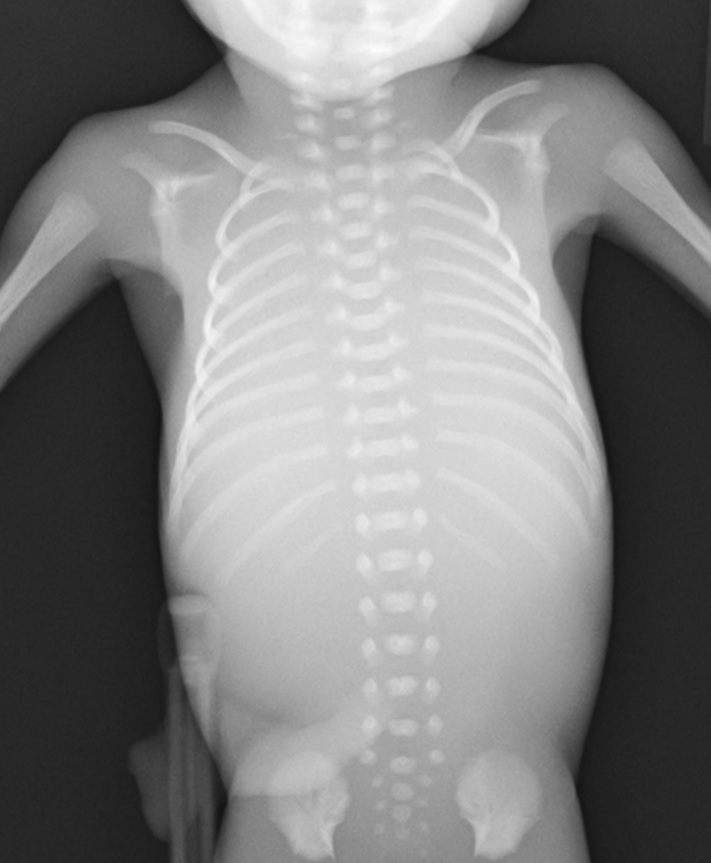

babygram-casus2

babygram-casus3